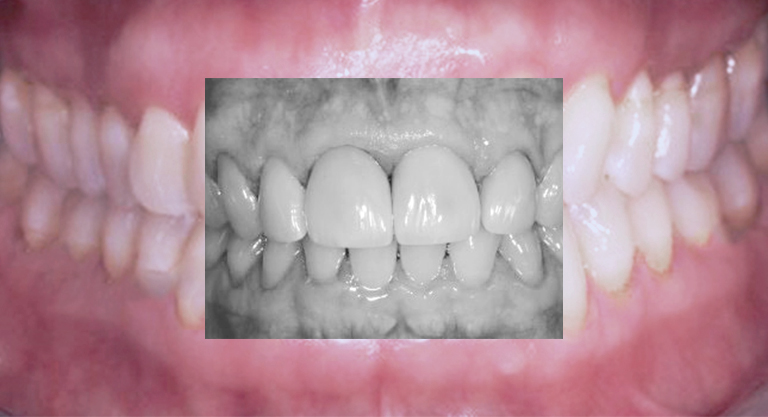

Ästhetisch, rekonstruktive Kronen-Brückenversorgungen

Prothetische Rehabilitation: Zahn- oder Implantat-getragen